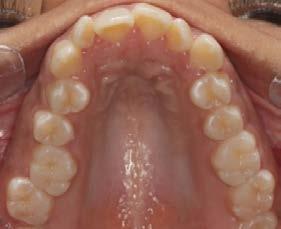

Objetivo: presentar un caso clínico de paciente con mordida abierta anterior, clase II y deglución atípica tratada con aparatología fija ortodóntica.

Caso clínico: paciente femenino de 19 años, patrón dolicofacial, perfil convexo, clase II esqueletal debido a una retrusión mandibular, mordida abierta anterior esqueletal, clase II molar, clase canina no establecida por mordida abierta, apiñamiento severo superior e inferior y deglución atípica.

Resultados: obtención de una clase canina I y clase molar II funcional, se corrigieron las sobremordidas horizontal y vertical, y se logró la coincidencia de líneas medias facial y dental. El manejo de la mordida abierta anterior se llevó a cabo por medio de la corrección del hábito de deglución atípica con la ayuda de spikes de resina, elásticos intermaxilares y arcos utility, y se obtuvieron buenos resultados estéticos, dentales y funcionales.

Al examen intraoral se observa arcada dental incompleta; con ausencia de órganos dentales 16 y 27 (Figura 1).